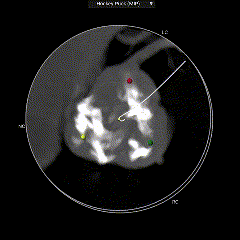

CT动态预览

主动脉根部测量

瓣上结构测量

冠脉阻挡风险、左室大小及横位心评估

外周血管入路评估